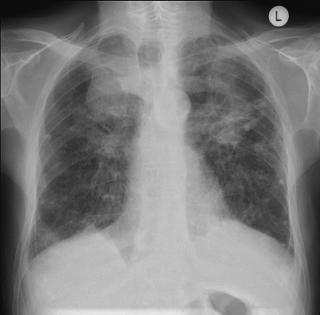

Обследование проводится в прямой и боковой проекциях грудной клетки, с прицельной съёмкой подозрительных зон, а при необходимости — в косых проекциях, в режиме обзорной рентгенографии для выявления прямых признаков пневмосклероза. Цель обследования — выявление рентгенологических сигналов фиброзно-склеротических изменений лёгочной ткани, оценка их распространённости, локализации и влияния на архитектуру лёгких и прилежащие структуры.

Рентгенография выявляет следующие признаки пневмосклероза:

Деформация лёгочного рисунка с неструктурными линейными и сетчатыми тяжами, сигнализирующими о разрастании соединительной ткани в межальвеолярных и перибронхиальных перегородках.

Неравномерное уплотнение лёгочной ткани с участками повышенной и пониженной прозрачности, отражающее участки уплотнения и компенсаторной эмфиземы.

Втяжение плевры и междолевых щелей с образованием втяжных линий к области наиболее выраженного склероза.

Уменьшение объёма поражённого участка лёгкого или целой доли с повышением прозрачности окружающих отделов за счёт компенсаторного перераздувания.

Уплотнение и деформация корней лёгких, свидетельствующие о вовлечении перибронхиальных и периваскулярных структур.